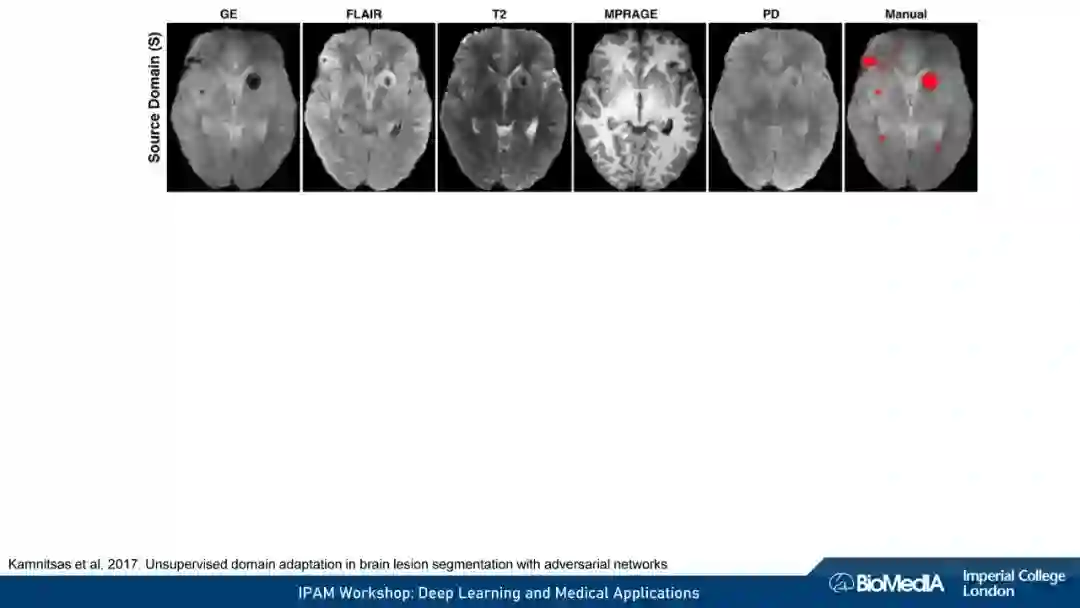

我们使用因果推理来阐明医学成像的关键挑战:1) 数据稀缺,即高质量注释的有限可用性 2) 数据不匹配,即训练有素的算法可能无法在临床实践中推广。我们认为,图像、注释和数据收集过程之间的因果关系不仅会对预测模型的性能产生深远的影响,甚至可能决定首先应该考虑哪种学习策略。例如,半监督可能不适合于图像分割——这可能是我们在医学图像分析中因果关系考虑的一个令人惊讶的见解。我们的结论是,对于基于机器学习的图像分析的成功至关重要的是,研究人员要能意识到并解释他们的数据背后的因果关系。